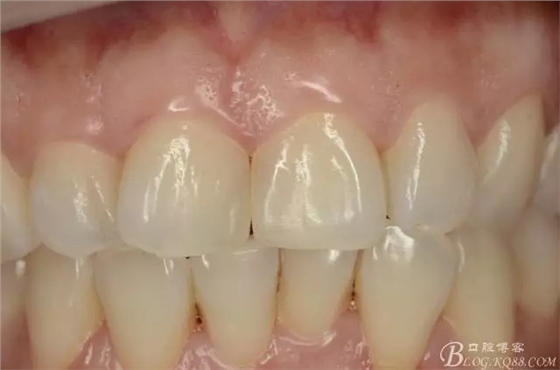

3個(gè)月后復(fù)診照片:

(3月后復(fù)診,釉質(zhì)再礦化完全,顏色穩(wěn)定)